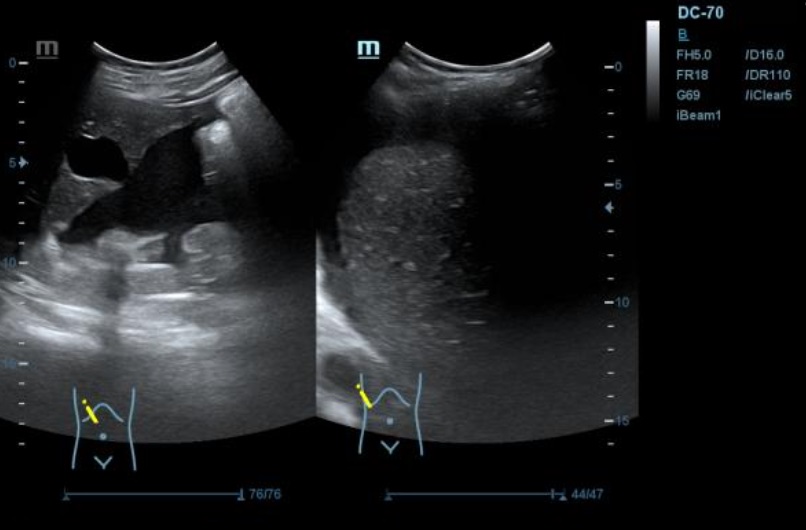

Ecografía: se observa presencia de líquido ascítico, e imagenes en hipomesogastrio hipo e hiper ecogénicas, tabicadas algunas, con efecto masa, con vascularizacion al Doppler que sugieren carcinoma de ovario.

Neoplasia de ovario bilateral con carcinomatosis peritoneal y omental, implantes peritoneales y subcapsulares hepáticas y abundante ascitis.